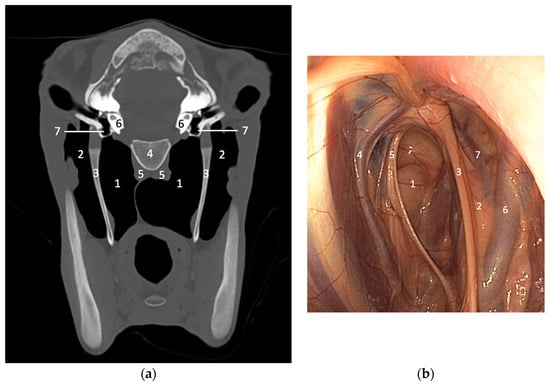

2.3. Cross-Sectional Imaging